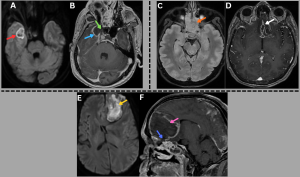

Fig 10: Cases 1–3: Intracranial Abscesses....

Case 1 -

A 48-year-old male with uncontrolled diabetes mellitus and recent corticosteroid use presented with fever, headache, and altered sensorium.

Axial diffusion-weighted imaging (DWI) and apparent diffusion coefficient (ADC) images (A), along with a post-contrast T1-weighted MRI image (B), demonstrate a diffusion-restricting abscess in the right temporal lobe (red arrow) with peripheral rim enhancement (blue arrow) and a central nonenhancing core, showing direct continuity with adjacent sinusitis (green arrow).

..........Case 2 -

A middle-aged male with uncontrolled diabetes mellitus and recent corticosteroid use presented with fever, headache, and altered sensorium.

Axial T2/FLAIR MRI image (C) demonstrates near-complete opacification of the ethmoid sinuses (orange arrow). Axial post-contrast T1-weighted MRI image (D) demonstrates a peripherally enhancing subdural collection along the anterior falx with additional enhancing collections in the basifrontal region (white arrow).

...........Case 3 -

A 48-year-old diabetic male presented with fever, headache, and new-onset behavioral changes.

Axial DWI image (E) and sagittal post-contrast T1-weighted MRI image (F) demonstrate a diffusionrestricting abscess in the left frontal lobe (yellow arrow) with peripheral rim enhancement and a central nonenhancing core (pink arrow), showing direct extension from ethmoidal sinusitis (blue arrow).